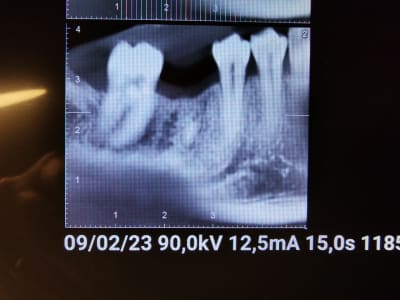

Dans un cas comme celui-ci ,faites vous l'ablation de l'apex résiduel en même temps que la pose de l'implant au risque de perdre la stabilité primaire de l'implant, ou , faites vous l'ablation de l'apex et différez à deux mois la pose de l'implant?

Perso je vire l’apex et je pose le même jour. Y’a pas mal d’os en dessous. Faut juste éviter te te laisser embarquer en médial quand tu feras ton forage, sinon la position de ton implant sera pas top

En plus en commençant ton forage tu vas naturellement tomber sur le bout d'apex, ce qui facilitera l'ext, sans avoir à faire une alveolectomie devastatrice.